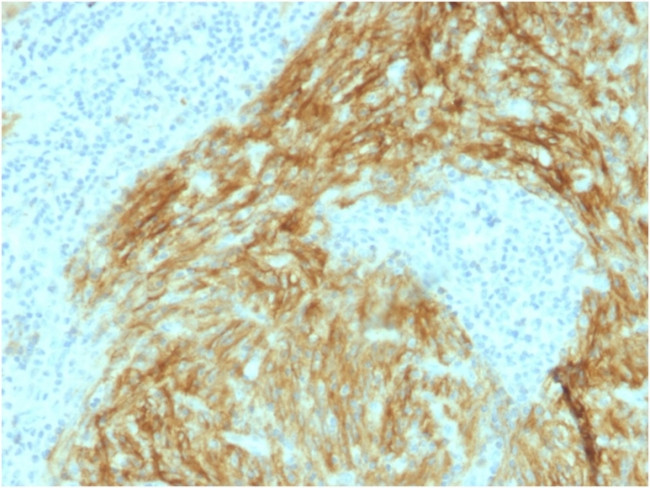

CD21 (Mature B-Cell and Follicular Dendritic Cell Marker) Antibody in Immunohistochemistry (Paraffin) (IHC (P))

CD21 (Mature B-Cell and Follicular Dendritic Cell Marker) Antibody (1380-MSM2-P0) in IHC (P)

Formalin-fixed, paraffin-embedded human Follicular Dendritic Cell Sarcoma stained with CD21/CR2 Mouse Monoclonal Antibody (CR2/1952). {{ $ctrl.currentElement.advancedVerification.fullName }} 验证信息 View more